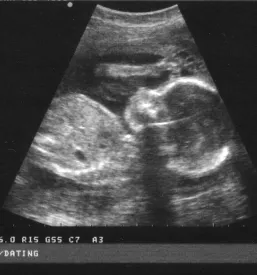

V naši ambulanti se predvsem trudimo, da bi imeli čimbolj profesionalen, diskreten in strokoven pristop k problematiki, ki jo obravnavamo. Da pa bi našim pacientkam zagotovili le najboljše, se nenehno izobražujemo in skušamo dosledno slediti sodobnim smernicam, ki se izoblikujejo tako pri nas kot tudi v tujini. Zato je med drugim na voljo tudi 3d 4D UZ - oziroma ultrazvočni pregled ploda.

V sklopu svoje ambulante ponujamo ginekološko in porodniško dejavnost, poleg tega svojim pacientkam nudimo preglede dojk in različne oblike ultrazvoka. Samoplačniško izdelamo tudi 3D 4D UZ.